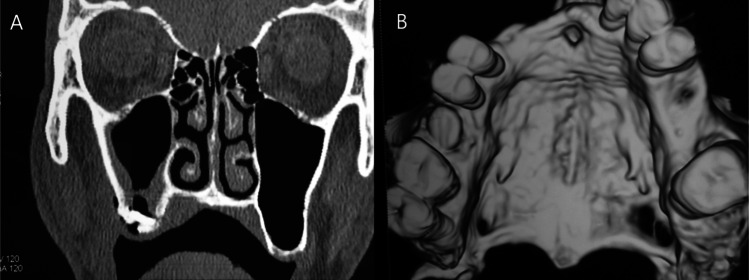

One clinical complication oral surgeons encounter is oroantral communication (OAC) with progressive formation of oroantral fistula (OAF). Among bone grafting materials, autogenous bone is still considered the gold standard in grafting oral and maxillofacial regions. To evaluate clinically and radiographically the efficacy of Calcium phosphate (Vital-Os) bone cement in stabilizing an autogenous bone graft in repairing an oroantral fistula. The study recruited 20 patients with an oroantral fistula ranging from 4-10 mm diameter. Ten patients were treated by grafting the defect with bone graft harvested from the chin area and closure of oroantral by buccal advancement flap and Vital-Os Bone cement (Study group), and ten patients were treated without Vital-Os Bone cement (Control group). All patients came for postoperative follow-up at the 1st, 3rd, and 6th months. Visual Analogue Scale (VAS) in the study group was significantly lower than the control group one week and one month postoperatively (p = .007, .004; respectively). Failure of the oroantral fistula closure was significantly lower in the study group (p = .025). The closure of an oroantral fistula is recommended through the use of an autogenous bone graft harvested from the chin region, supplemented by the application of injectable VitalOs bone cement to secure the graft at the recipient site.